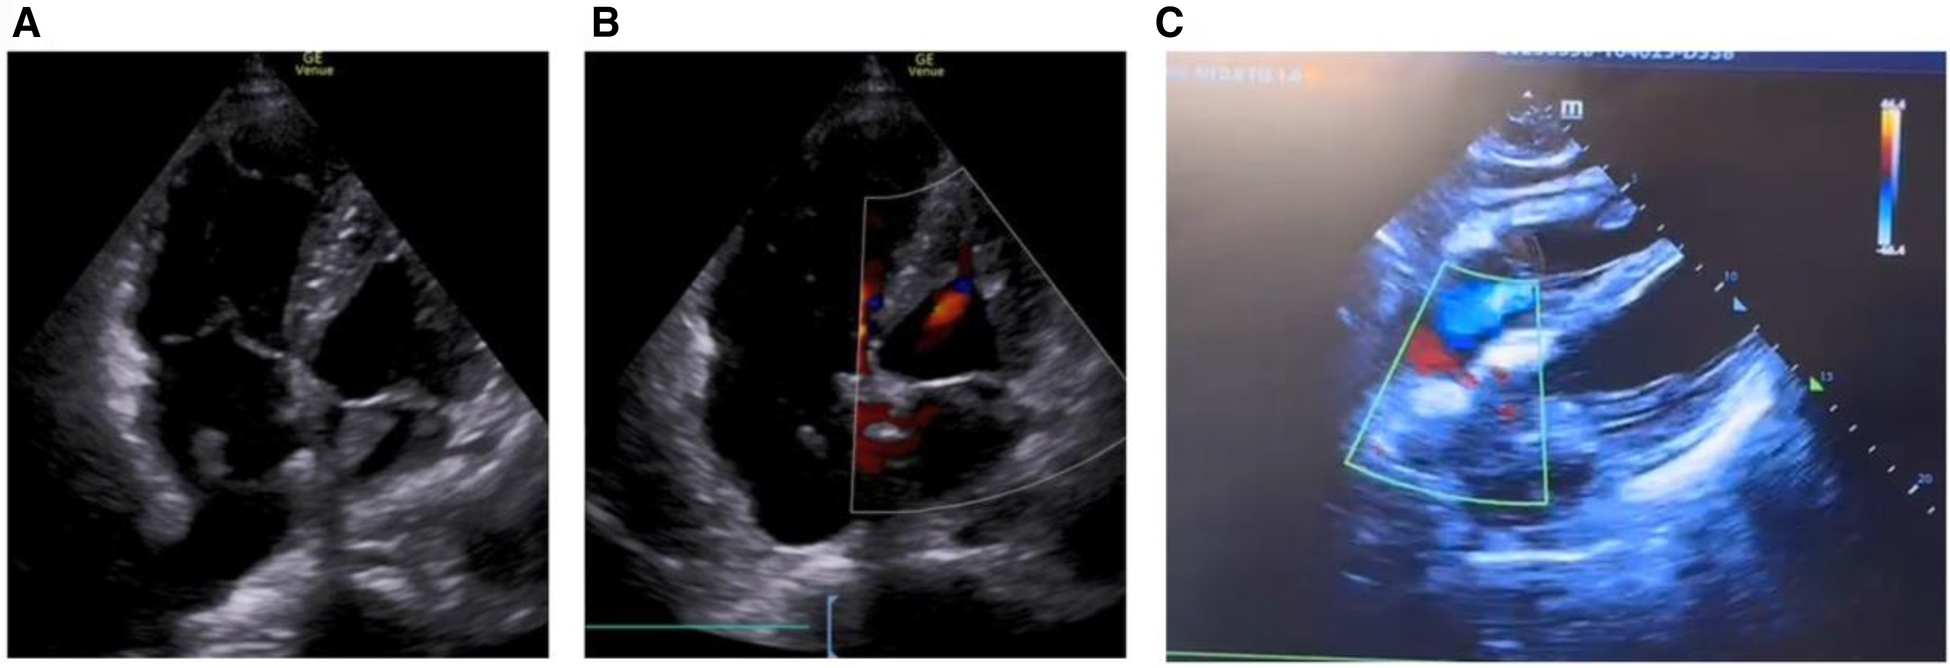

On March 28, 2023, at 14:20, the patient was transferred to our hospital's Intensive Medicine Department. The patient had a temperature of 36°C, a pulse of 98 beats/min, a respiratory rate of 20 breaths/min, and blood pressure of 92/62 mmHg (under the combined auxiliary treatment with norepinephrine, epinephrine, and dobutamine), Vasoactive Inotropic Score (VIS): 105 points. Pulse oxygen saturation (SpO2) was 99%. Blood gas analysis showed a pH of 7.49, blood oxygen concentration of 50%, carbon dioxide partial pressure of 26.00 mmHg, oxygen saturation of 99%, oxygen partial pressure of 106.00 mmHg, blood lactate level of 3.5 mmol/L, and an oxygenation index of 212.00 mmHg. The patient's laboratory test results were Creatinine 176 umol/L, D-dimer >20 mg/L, N-terminal pro-B-type natriuretic peptide (NT-proBNP) 14,535 pg/ml, and cardiac troponin I 1.12 ng/ml. The ECG results indicated a sinus rhythm, abnormal Q waves (Ⅲ, aVF), and T wave changes. Echocardiography showed a left atrial anteroposterior diameter of 26 mm, a right atrial anteroposterior diameter of 46 mm, a left ventricular end-diastolic diameter of 40 mm, a right ventricular anteroposterior diameter of 23 mm, a left ventricular ejection fraction of 54%, thrombi in both atria, severe pulmonary arterial hypertension (70 mmHg), and an atrial septal defect width of approximately 4.1 mm (Figure 2, Table 1). Thrombosis formation was seen in the bilateral popliteal veins (complete occlusion). Pulmonary artery CT angiography indicated bilateral multiple PEs and intra-atrial occupying lesions in both atria (Figure 3).

Figure 2

Echocardiogram shows biatrial thrombosis, atrial defect or patent foramen ovale. (A) Apical four-chamber view, biatrial thrombus; (B) apical four-chamber view, small atrial defect or patent foramen ovale; (C) four-chamber heart view of the xiphoid process, atrial defect or patent foramen ovale.